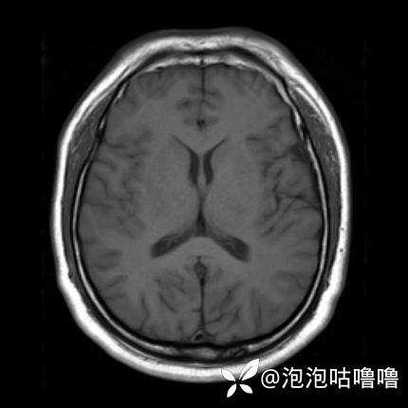

再看“在哪里”——定位病灶

如果CT上已经能看到低密度区,或者医生结合症状高度怀疑是脑梗,下一步就是定位。

- 看层面: CT片子是从下往上(脚到头)一层一层扫描的,每一层都有编号(如层面1、层面2...),你需要找到病灶在哪一层。

- 看左右: 片子上通常会标有“L”(左)和“R”(右),对照患者自己的左右,确定病灶在左侧还是右侧大脑。

- 看具体位置:

- 大脑半球: 是在额叶、顶叶、颞叶还是枕叶?

- 脑干: 是在脑桥、中脑还是延髓?(脑干梗塞非常危险)

- 小脑: 位于后颅窝。

为什么定位重要: 不同部位的血管堵塞,会导致不同的症状,左侧大脑中动脉堵塞,可能导致右侧偏瘫、失语;右侧大脑中动脉堵塞,可能导致左侧偏瘫、空间忽略症等。